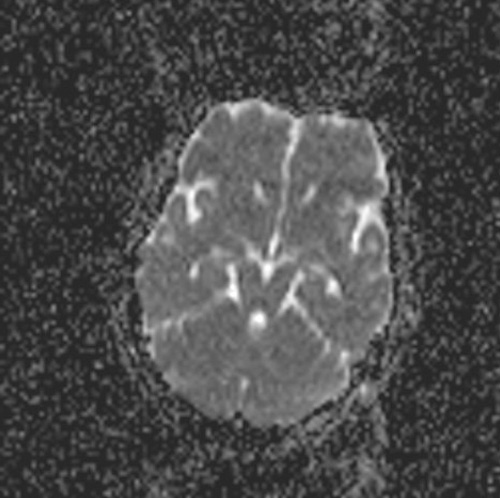

35 year old female with c/o sensory loss over left side of the body including face.

QUIZ - 2 (20th Aug 2013)

17 Months child with developmental delay.